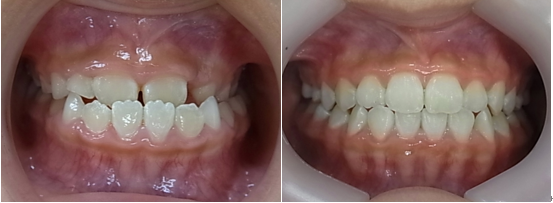

8歳の女子 受け口(下顎前突)

術前

術後

7歳の女子 受け口(下顎前突)

いずれも、顎のラインがスッキリしています。

これは、受け口が改善して筋肉の使い方が通常に戻ったために起こった変化です。

大人ではこの変化は起こりません。